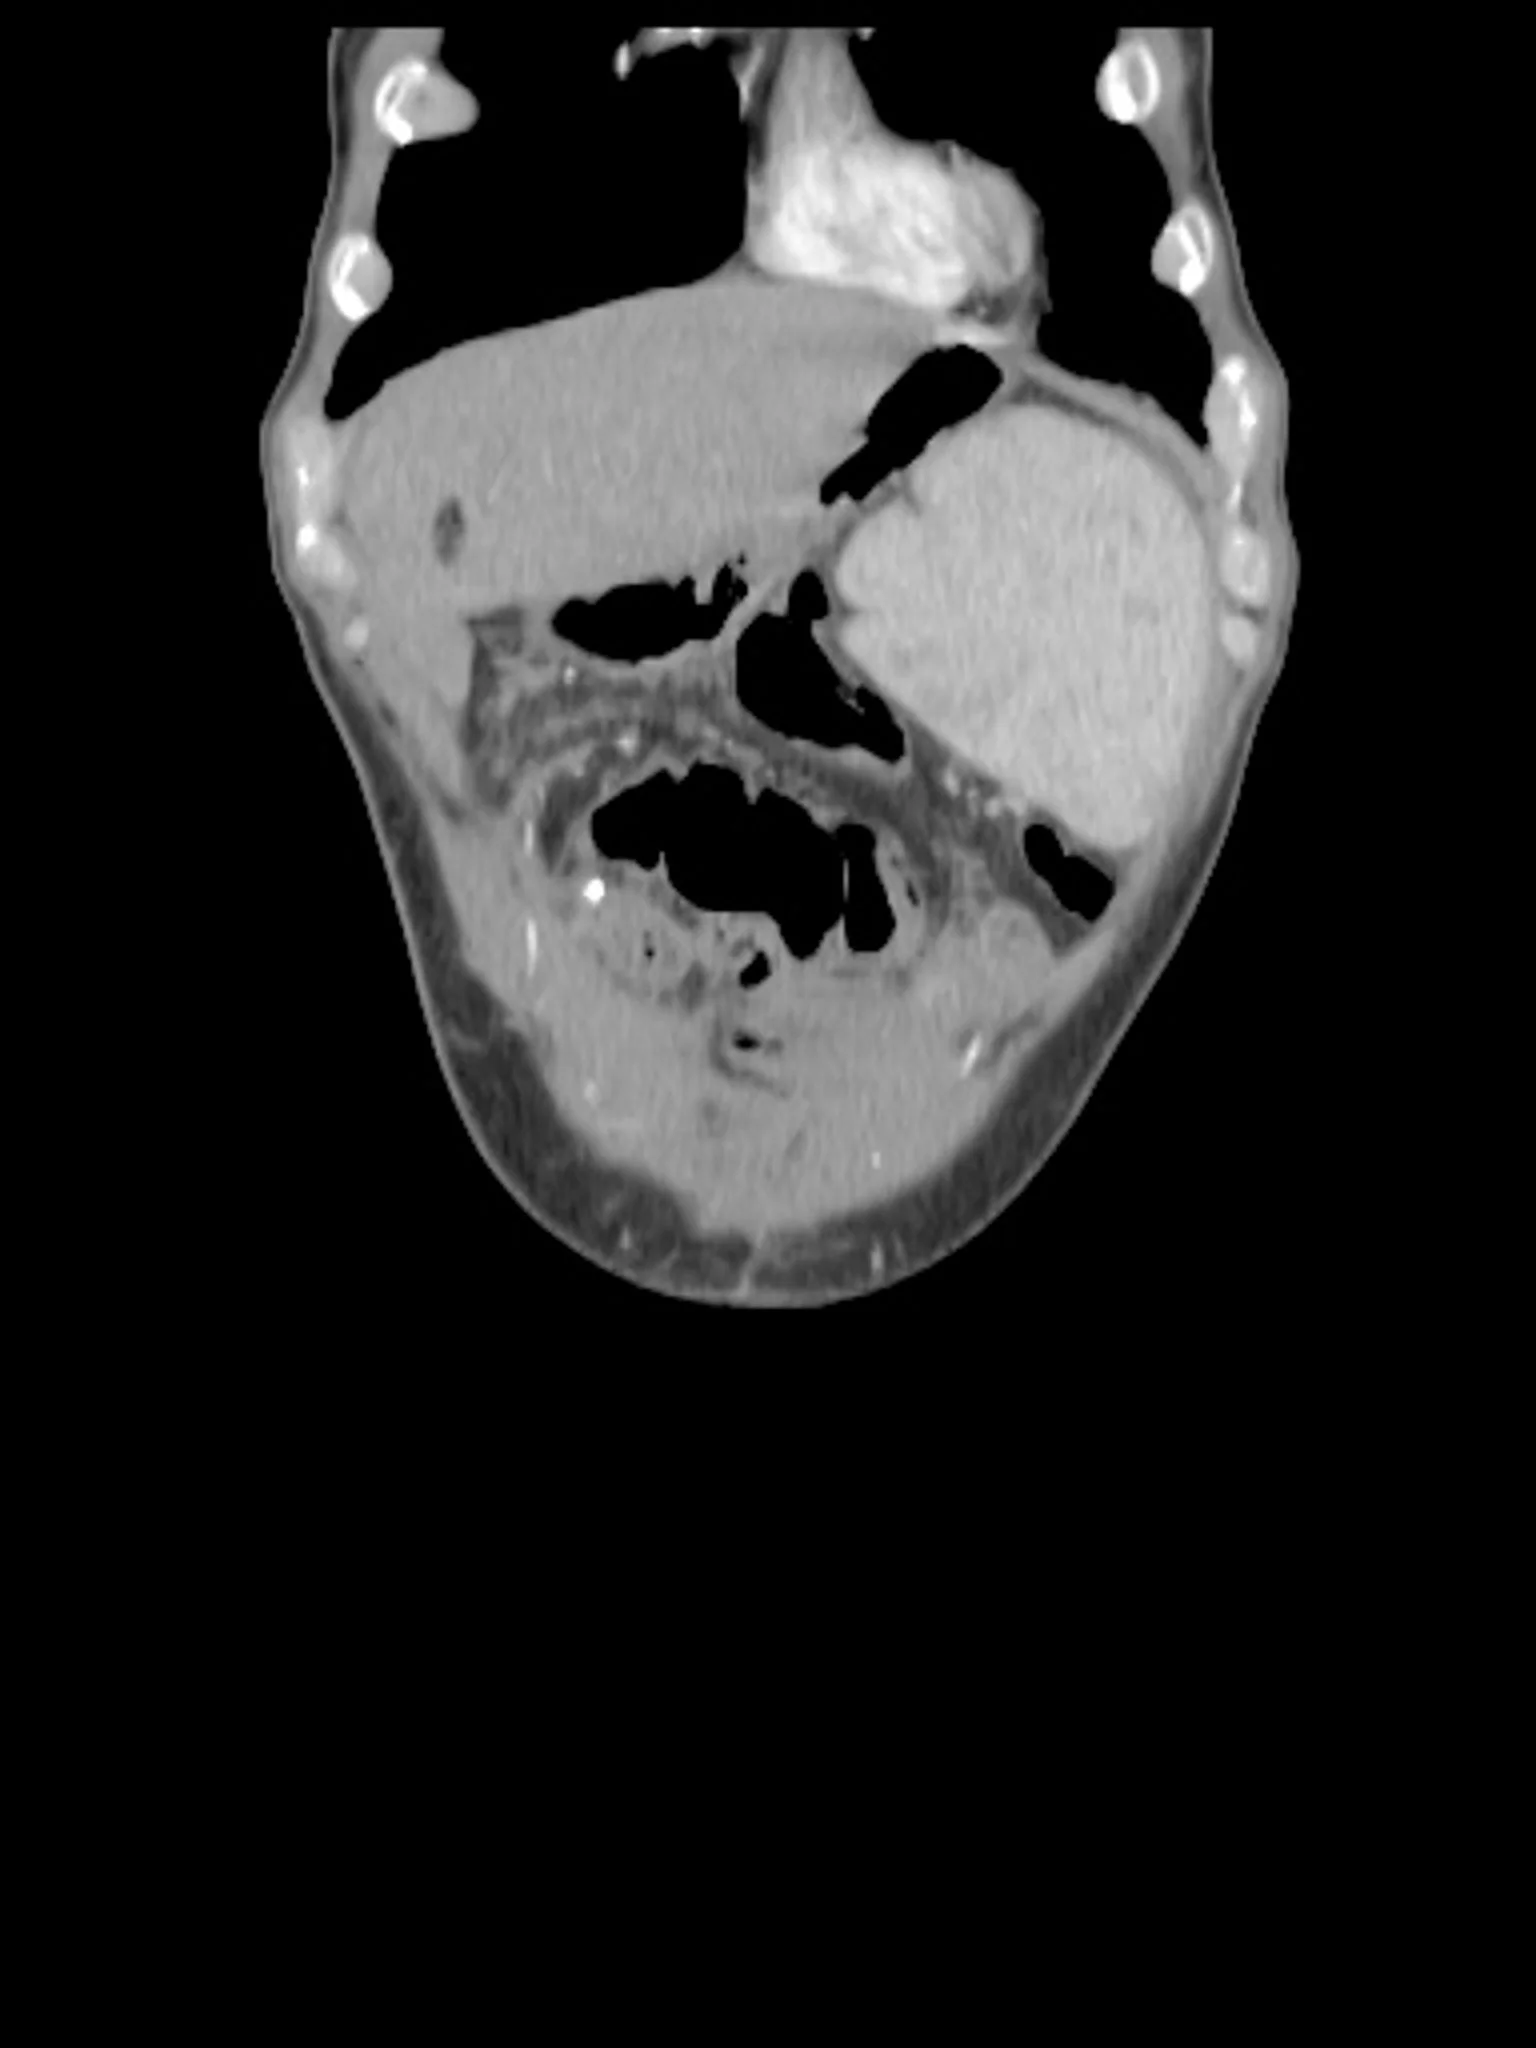

Around 10 million people worldwide live with Crohn’s Disease or Ulcerative Colitis — chronic, autoimmune conditions that affect the digestive system but leave scars everywhere: in the body, the mind, and human connections.

Those affected face shifting symptoms: pain, fatigue, malnutrition, chronic diarrhea, fever, and others.

On top of that come surgeries, invasive tests, evasive conversations with doctors. For life.